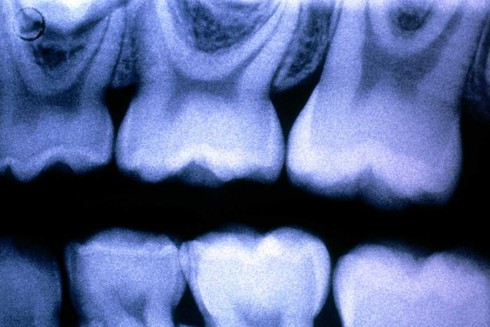

Men răng là lớp màu trắng sáng ở gần đầu của răng. Ảnh: Getty Images. |